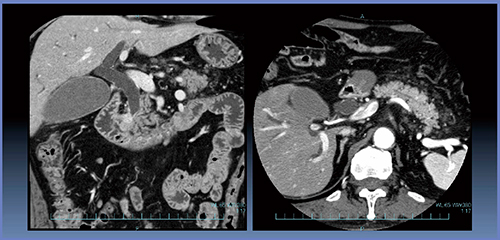

症例2は,膵頭部がんで術中にhard pancreasと判定され,術後膵液瘻なく経過した(図5)。Perfusion解析は,AF=37.4±3.0mL/min/100mL,MTT=41.7±2.3sとなった(図6)。

図5 症例2:膵頭部がん(no POPF)